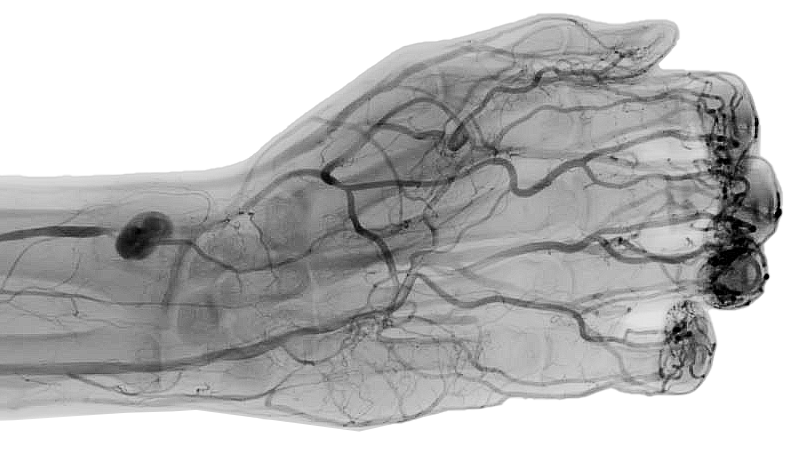

I am pleased to introduce my practice and services offered. I am a specialist vascular surgeon, interested in treating all arterial and venous conditions. In order to reduce the length of hospital stay and optimise patient outcomes, I adopt a patient-centred approach together with modern diagnostic and surgical techniques. Although I hope that this site may be of benefit to giving an overview of my services, vascular conditions are often complex, and are best evaluated face to face. Please arrange an appointment if you require a consultation.

Both minimally invasive (balloons and stents); open surgery; as well as a combination of both (hybrid) are individualised to the patient’s needs in the treatment of all vascular conditions, including: